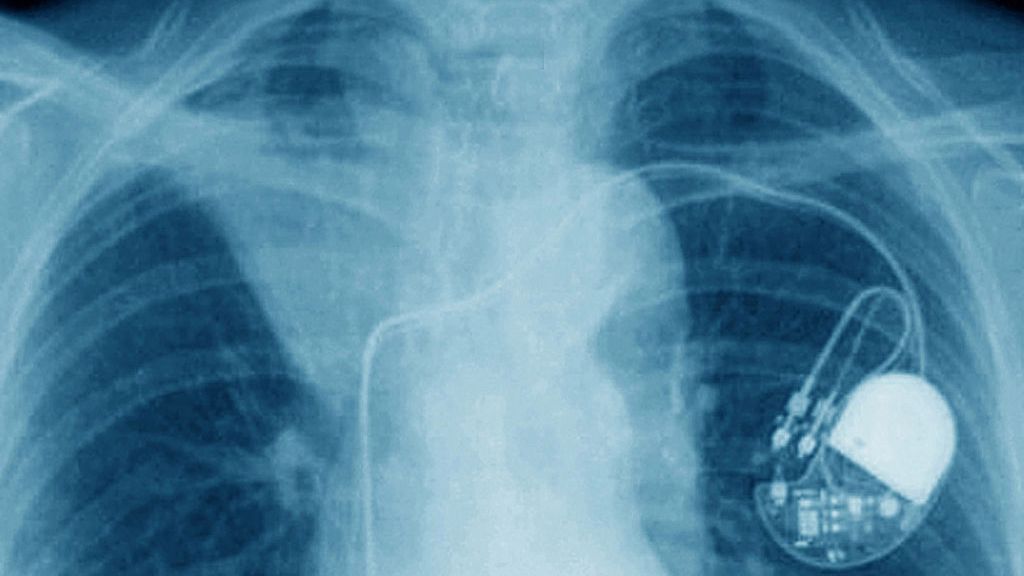

Według nowych badań opublikowanych w w czasopiśmie Heart Rhythm umieszczenie iPhone'a 12 na rozruszniku serca może wyłączyć jednostkę ratującą życie.

Jak podają naukowcy, wynika to w dużej mierze z pola magnetycznego wytwarzanego przez technologię ładowania MagSafe. Została ona zaprojektowana w taki sposób, by ułatwić ładowanie bezprzewodowe oraz doczepianie akcesoriów do iPhone'a 12. Niestety ten sam układ magnetyczny może uszkodzić lub całkowicie wyłączyć rozrusznik serca.

Jedyną dobrą wiadomością jest to, że zdaniem naukowców z Henry Ford Heart and Vascular Institute, MagSafe może uszkadzać jedynie rozruszniki firmy Medtronic. Niestety dla osób, które korzystają właśnie z tych urządzeń, korzystanie z iPhone’ów wciąż może być niebezpieczne.

• Po zbliżeniu iPhone'a do ICD nad lewym obszarem klatki piersiowej odnotowano natychmiastowe wstrzymanie terapii ICD, które utrzymywało się przez cały czas trwania testu - podają naukowcy. - Powielaliśmy eksperyment wielokrotnie, za każdym razem umieszczając telefon w innej pozycji w pobliżu rozrusznika. Efekt był zawsze taki sam.

Naukowcy podkreślają, że samo korzystanie z iPhone’a 12 nie jest dla osób z rozrusznikami serca ryzykowne. Jednak zdecydowanie nie zalecają noszenia telefonu przy piersi, np. w kieszonce koszuli. Apple zresztą już odniósł się do problemu i poinformował, że "magnesy i pola elektromagnetyczne emitowane przez ich urządzenia iPhone mogą zakłócać działanie urządzeń medycznych, takich jak rozruszniki serca i defibrylatory".